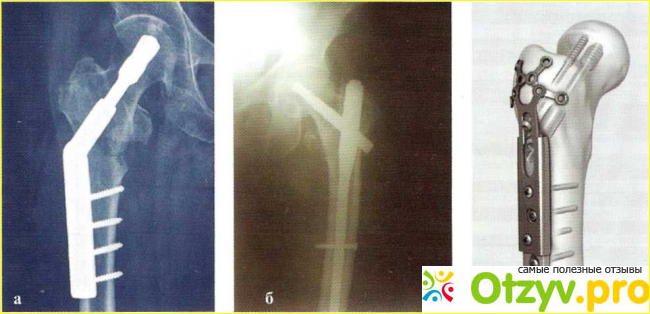

Это хирургическое вмешательство, при котором производится достаточно жесткая фиксация кости в зоне перелома. Для фиксации хирурги используют металлические стержни, различные конструкции из стали и системы с резьбой.

Все эти приспособления удерживают кость в правильном положении, обеспечивая её неподвижность; в результате шейка бедра имеет возможность для нормального сращивание.

Чаще всего остеосинтез проводят при переломе шейки бедра, но также эта методика может применяться и в лечении других переломов.